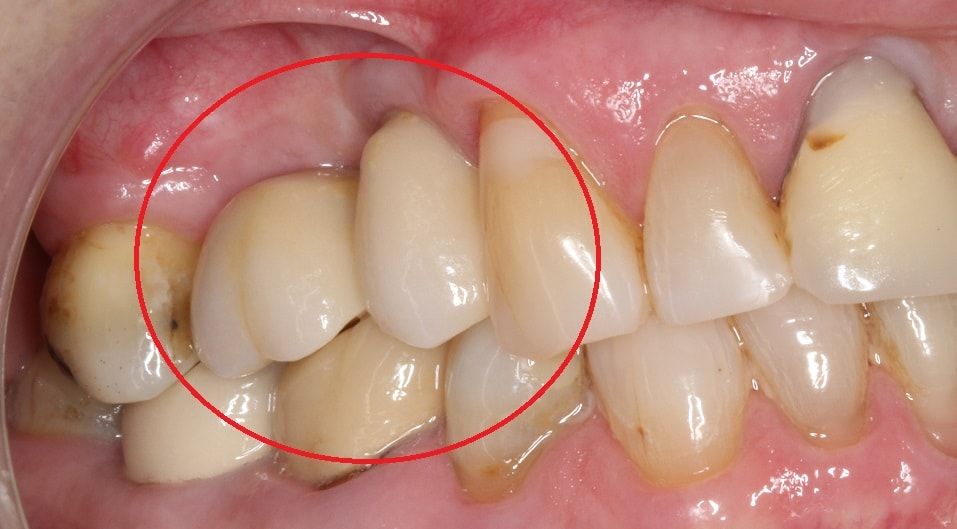

• до синус-лифтинга

• после синус-лифтинга

• после установки имплантатов в верхнюю челюсть

• коронки установленные на имплантаты